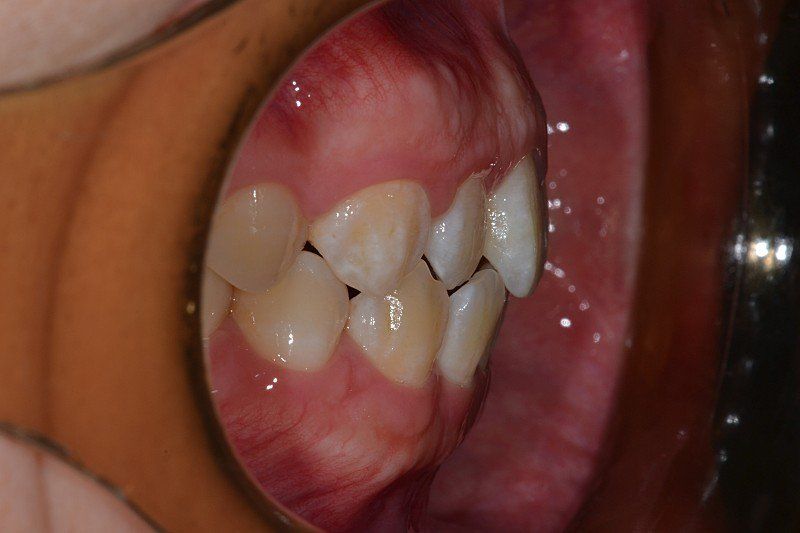

)치아 뼈가 전방으로 많이 나온 상태인가요?

)골격적으로 나온건가요?

1. 전방으로 많이 나왔다고 볼 수도 있지만 심미적으로 봤을 때 치료를 하지 않아도 되는 정도입니다. 본인이 현재 안모에 불만족스럽다면 이는 치료의 대상입니다.

2. 해당 정도로는 교정으로 개선이 불가능하며 양악을 하셔야 합니다.